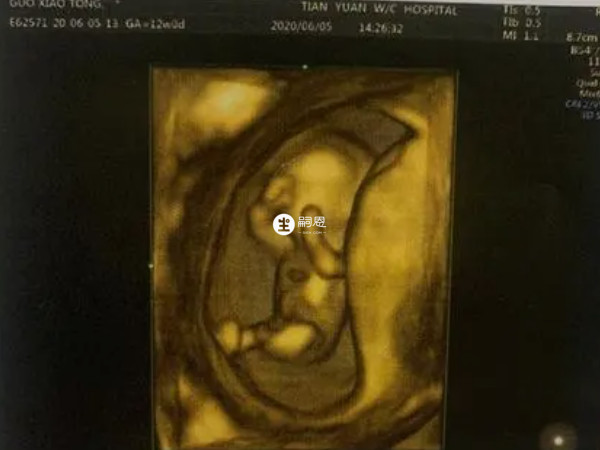

对于孕妇来讲,大多都会在孕12周左右做NT检查,很多人表示NT单子能够看出胎儿的性别。其实在NT检查单上面,怀女儿的特征和怀儿子的特征是不一样的,相信有许多的朋友是想要生女儿的。已生女儿的NT单子什么样,来看看已生女儿的网妈们,公布出来的女宝NT单子上比较明显的几个特征:

孕12周时,胎儿的外生殖器已经初步发育,而由于男女之间存在差异,因此在B超下表现也不同,如果孕妇怀的女孩,那么在图像上会看到有明显的三条线,这是女孩的性别特征,若是怀的男孩,会看到有三个亮点,或者是一个小突起,这是男孩的性别特征。

可以通过尾椎与身体所成角度进行判断,胎儿在11周左右,无论男女,在双腿之间会有一个生殖结节的组织,到孕12周时男女之间在B超下就会形成差异,如果NT图像上尾椎与躯干平行,中间几乎为零度角,那就是生女儿,若身体呈45度角,后脊背柱形成圆弧状,那就是生儿子。